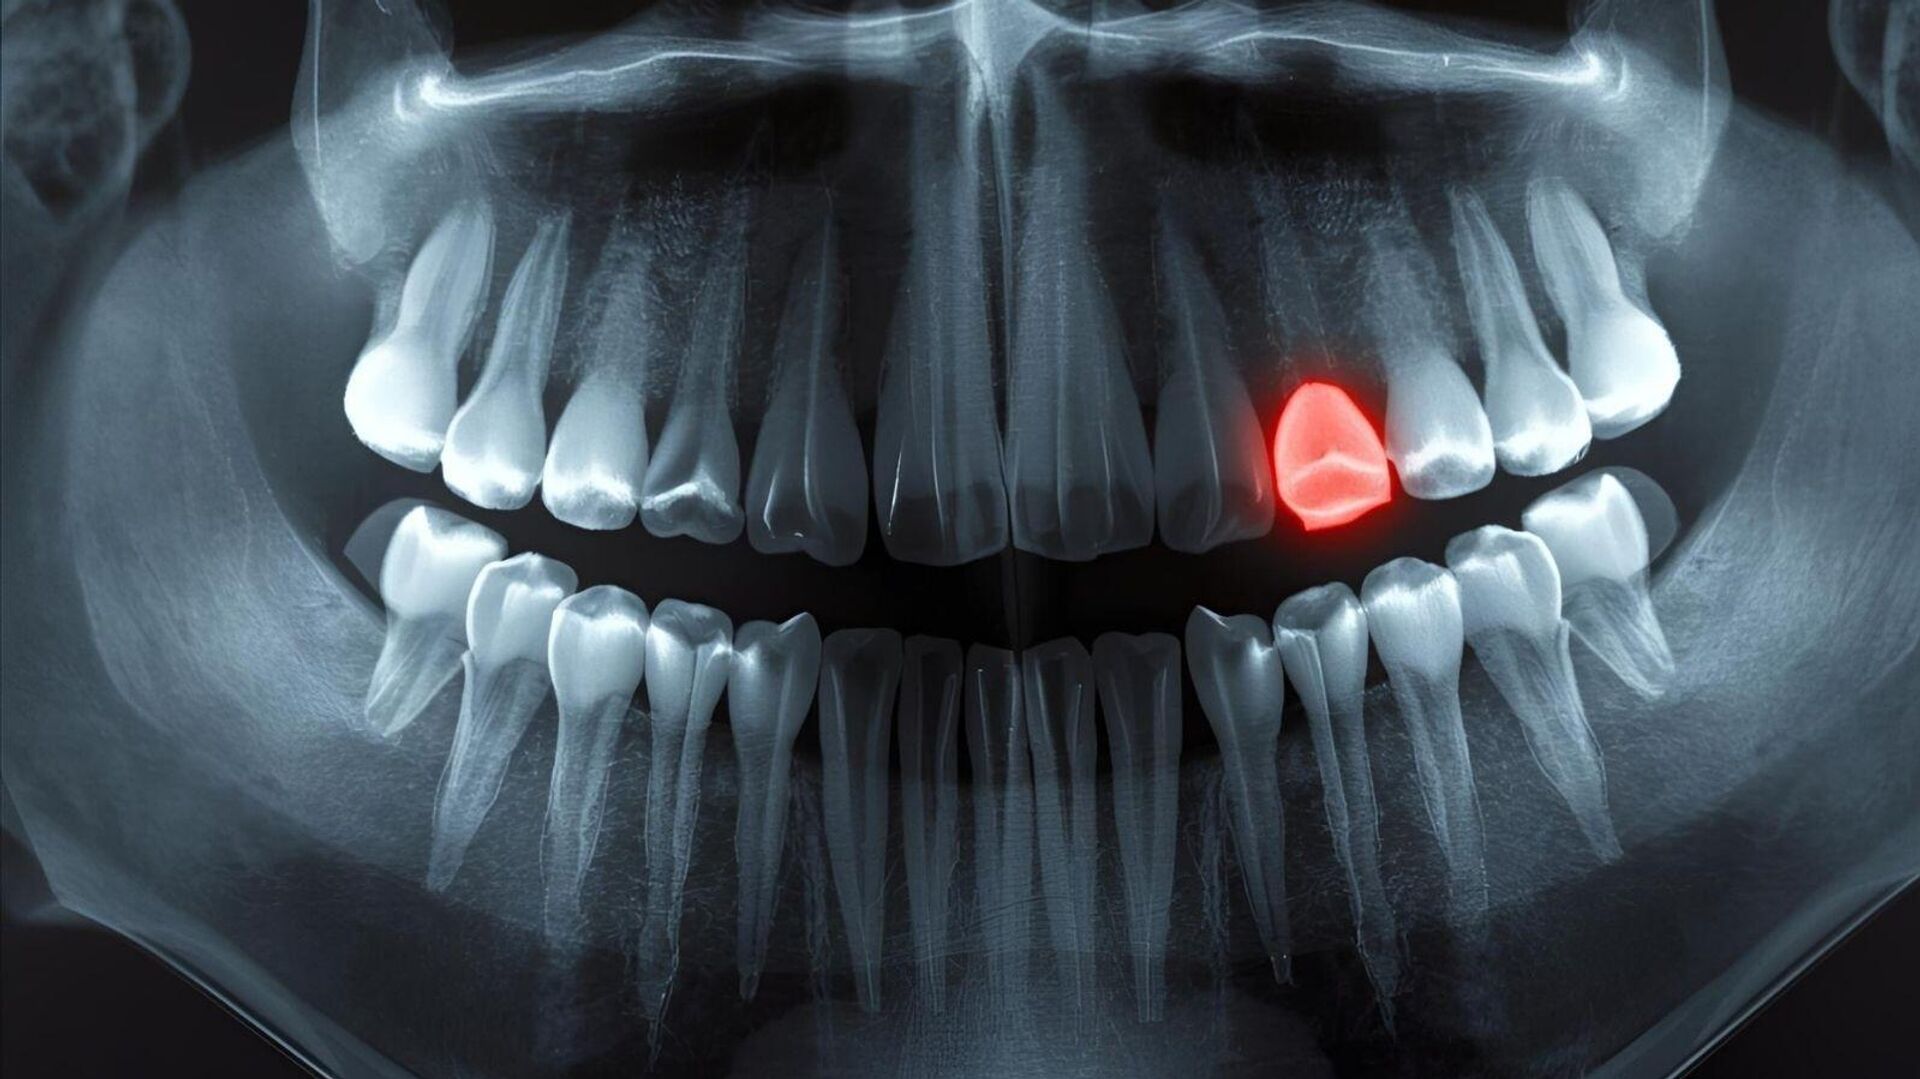

11:03 09.09.2025 (güncellendi: 12:22 09.09.2025) Japonya’dan araştırmacılar, insanlarda dişin yeniden oluşumunu mümkün kılabilecek bir deneysel ilaç üzerinde umut verici ilerlemeler kaydediyor. Klinik deneyler başarılı olursa 2030 yılına kadar tedavi geniş bir hasta grubuna ulaşabilir.

Kemikler kırıldığında kendilerini yeniden büyütebilir, ancak dişler aynı şansa sahip değildir. Bu nedenle dünya genelinde milyonlarca insan dişsizlik sorunu yaşıyor.

Ama dişler kemik değil. Benzer maddelerden yapılmış olsalar da ve insan vücudunun en sert materyali olsalar da, kendilerini onarma ve yeniden büyütme yetenekleri yok. Fakat Japon araştırmacılar, insan dişlerini yeniden büyütmeyi amaçlayan deneysel bir ilaçla ilerliyor. Deneyler Eylül 2024’te başladı.

Bu gelişme, “Uterine sensitization–associated gene-1 (USAG-1)” adı verilen ve gelinciklerle farelerde diş büyümesini engellediği gösterilen özel bir antikor üzerine yıllar süren çalışmaların ardından geldi.

2021’de Kyoto Üniversitesi’nden bilim insanları USAG-1 ile kemik morfojenetik protein (BMP) adı verilen moleküller arasındaki etkileşimi bozan monoklonal bir antikor keşfettiler.

Kyoto Üniversitesi’nden Katsu Takahashi, “USAG-1’in baskılanmasının diş büyümesine fayda sağladığını biliyorduk. Bilmediğimiz şey bunun yeterli olup olmayacağıydı” derken, insan ile oldukça benzer diş yapısına sahip gelinciklerde başarılı sonuçlar elde edildiğini aktardı.

Şimdi bilim insanları, benzerliği gerçekten görecek çünkü insanlar da aynı türde bir deneyden geçiyor. 11 ay sürecek bu çalışma, 30 ile 64 yaş arasında, en az bir dişi eksik olan 30 erkek üzerinde yapılıyor. İlacın etkinliğini ve güvenliğini göstermek için damar yoluyla uygulanacak. Şanslıyız ki, önceki hayvan deneylerinde herhangi bir yan etkiye rastlanmadı.

Her şey yolunda giderse, Kitano Hastanesi bu tedaviyi 2 ila 7 yaş arasında, en az dört dişi eksik olan çocuklara uygulayacak.

Hedef, 2030 yılına kadar diş yeniden büyütme ilacının yaygın olarak kullanılabilir hale gelmesi. Şimdilik bu tedavi doğuştan diş eksikliği yaşayan hastalara odaklanıyor olsa da, Takahashi bu yöntemin bir gün dişini kaybetmiş herkes için erişilebilir olmasını umuyor.